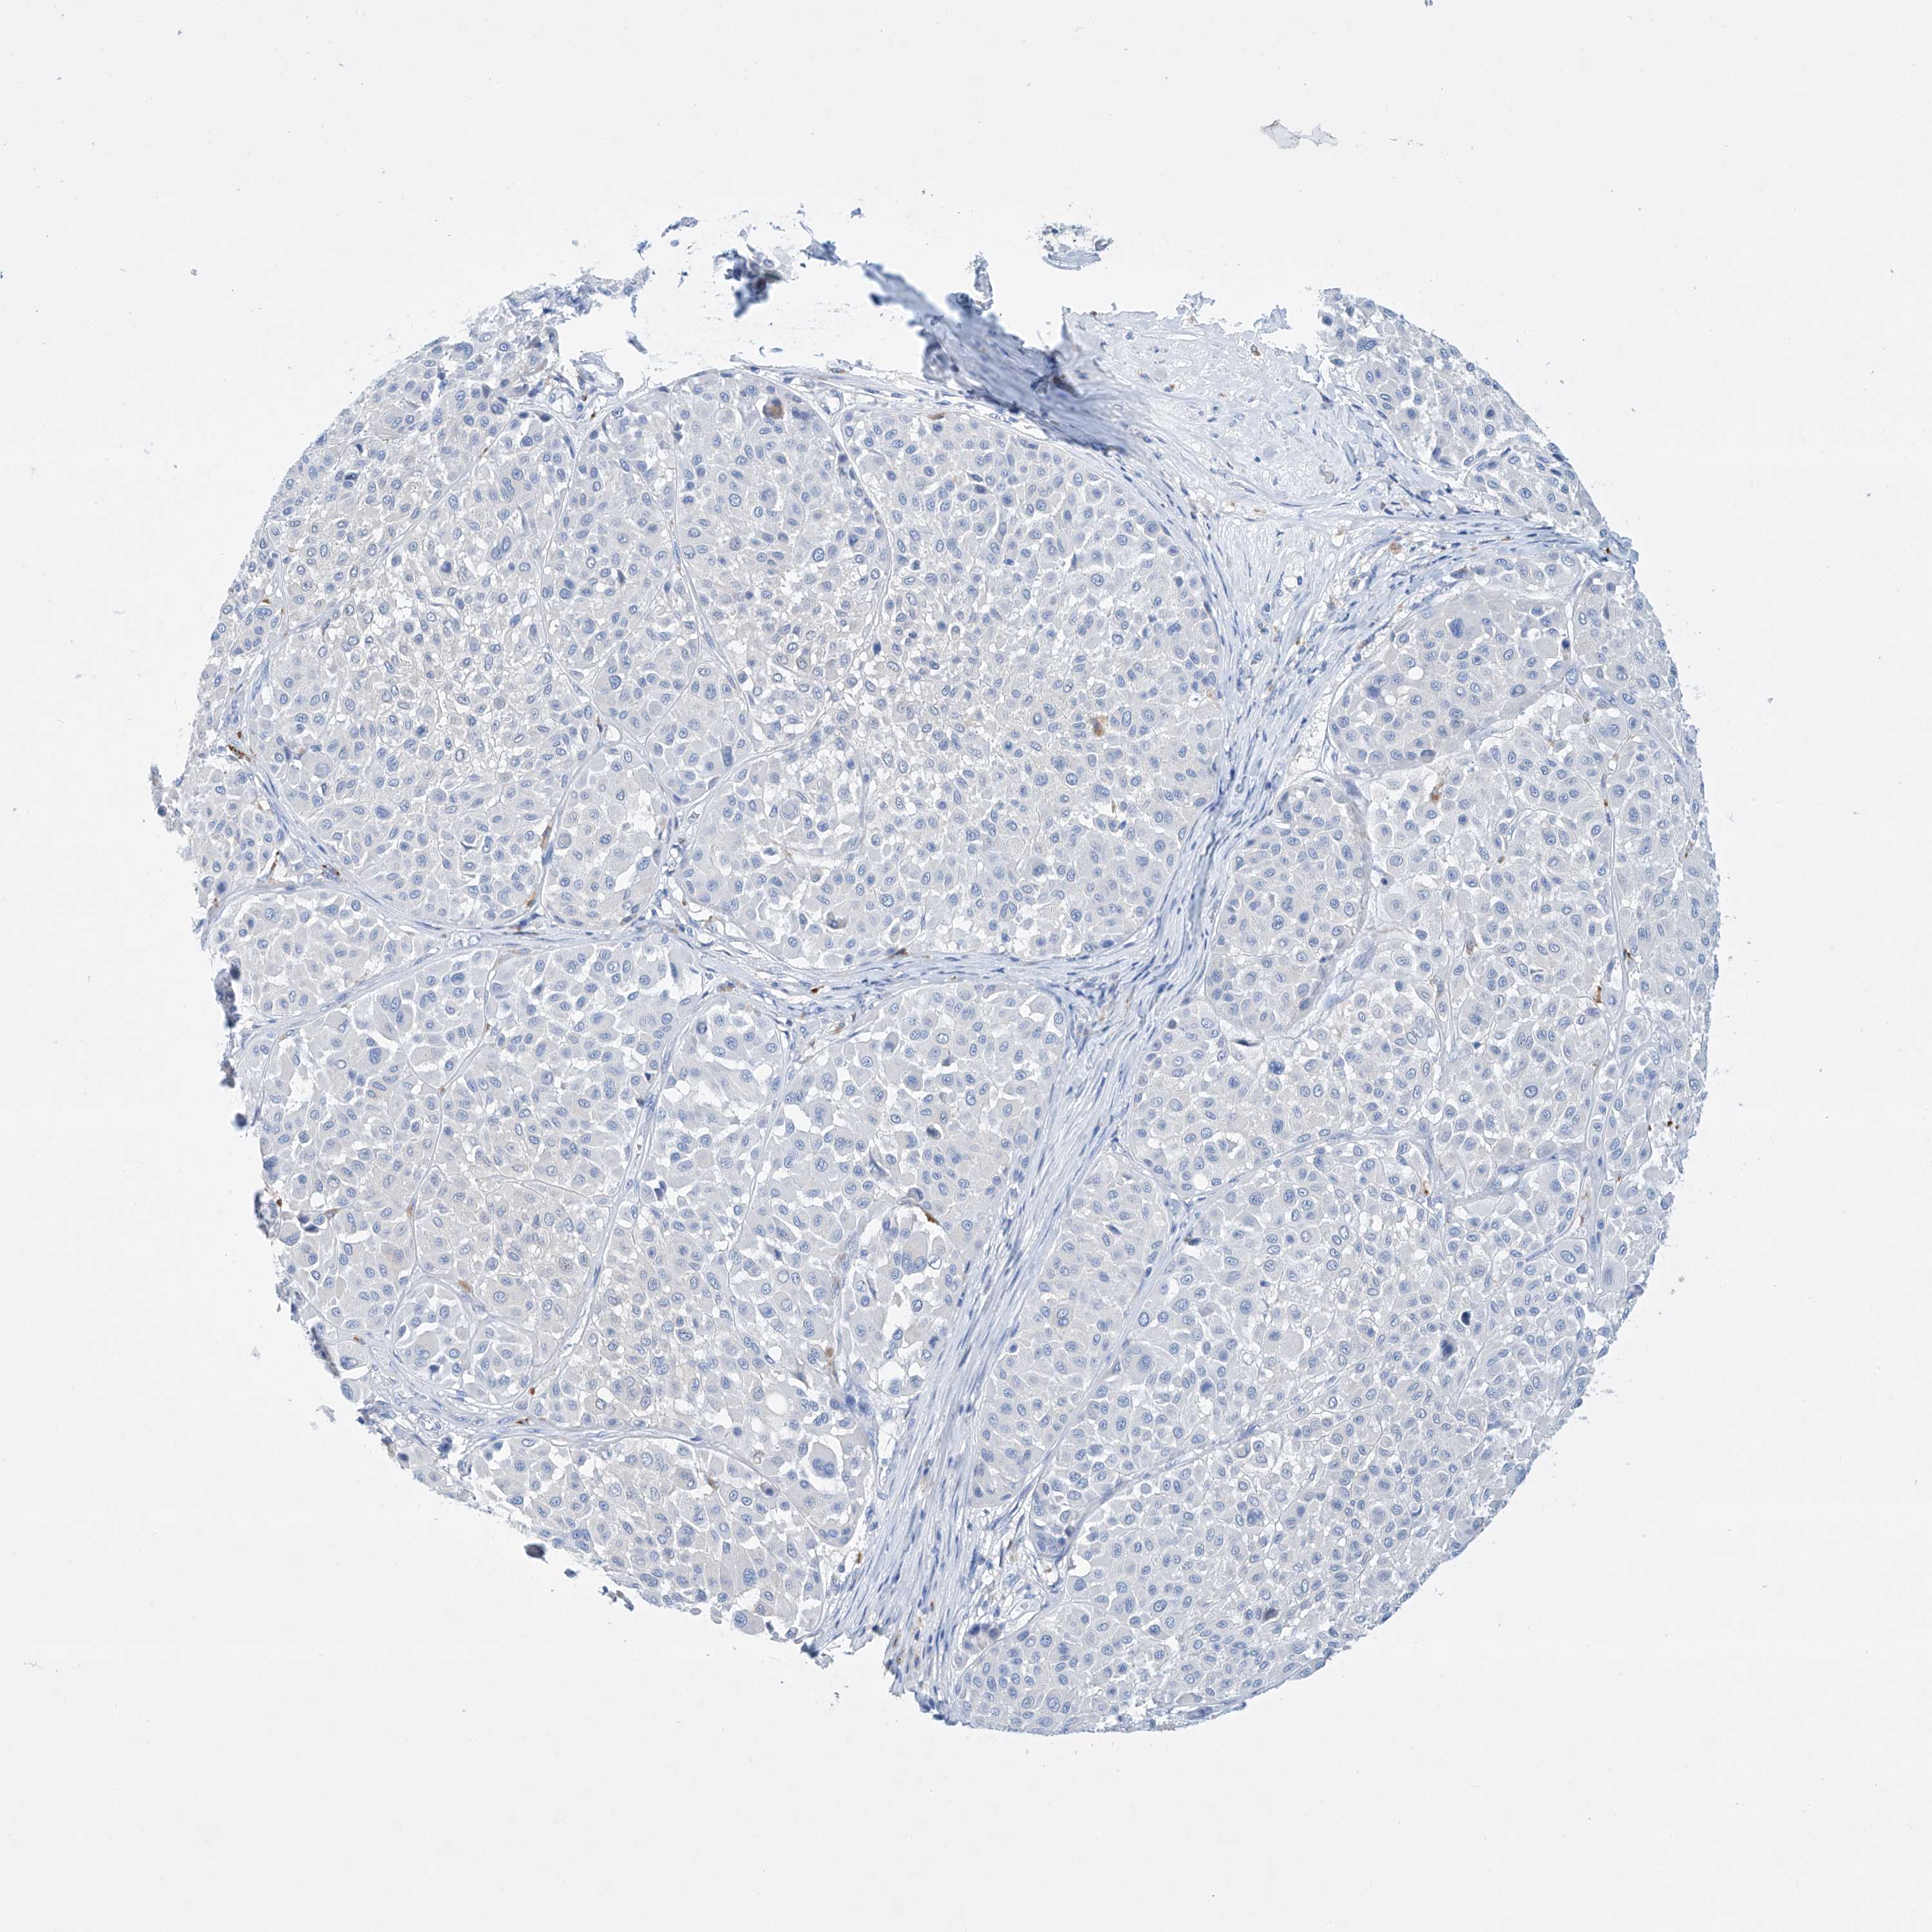

MELANOMA - Protein expressioni

A mouse-over function shows sample information and annotation data. Click on an image to view it in a full screen mode. Samples can be filtered based on level of antibody staining by selecting one or several of the following categories: high, medium, low and not detected. The assay and annotation is described here.

Note that samples used for immunohistochemistry by the Human Protein Atlas do not correspond to samples in the TCGA dataset.

Antibody stainingi

Antibody staining in the annotated cell types in the current human tissue is reported as not detected, low, medium, or high, based on conventional immunohistochemistry profiling in selected tissues. This score is based on the combination of the staining intensity and fraction of stained cells.

Each image is clickable and will lead to virtual microscopy that enables deeper exploration of all samples and also displays staining intensity scores, fraction scores and subcellular localization as well as patient and tissue information for each sample.

Antibody HPA030060

Antibody HPA030061

Staining

High

Medium

Low

Not detected

Intensity

Strong

Moderate

Weak

Negative

Quantity

>75%

75%-25%

<25%

None

Location

Nuclear

Cytoplasmic/membranous

Cytoplasmic/membranous,nuclear

Malignant melanoma, NOS

Malignant melanoma, Metastatic site